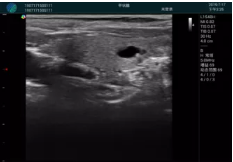

清晰顯示孕囊,通過軟件包計(jì)算孕齡7w+6d

M20實(shí)時(shí)引導(dǎo),術(shù)中清晰顯示孕囊被破壞和抽吸針的過程,清晰顯示吸引針

抽吸結(jié)束后縱切子宮,孕囊已被完全抽吸,未見明顯殘留

橫切子宮,發(fā)現(xiàn)右側(cè)宮腔靠近宮角處有少許脫模樣殘留

M20引導(dǎo)下,抽吸針找到右側(cè)宮角處再次清掃

二次抽吸后再次進(jìn)行超聲檢查,宮腔未見殘留,宮腔線清晰顯示

超聲引導(dǎo)下可視化人流是技術(shù)安全性的保障,一般對人流術(shù)設(shè)備預(yù)算不高,M20具備婦產(chǎn)科軟件包,且穿透力圖像質(zhì)量好,既滿足人流引導(dǎo)需要,也可用于床旁超聲的需求。